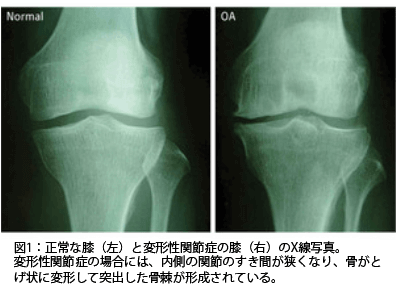

私たちの身体は筋肉と骨によって支えられています。骨の数は200数十本、それを結びつけ身体のさまざまな動きに対応して、スムーズに動かせる働きをしているのが関節です。しかし、加齢と共に徐々に軟骨が擦り減って、骨と骨がこすれあいその結果、骨が削られ変形を起こします。これが「変形性関節症」です。やがて腫れたり、熱が出たり、水が溜まるなどの炎症が起こり慢性化していきます。